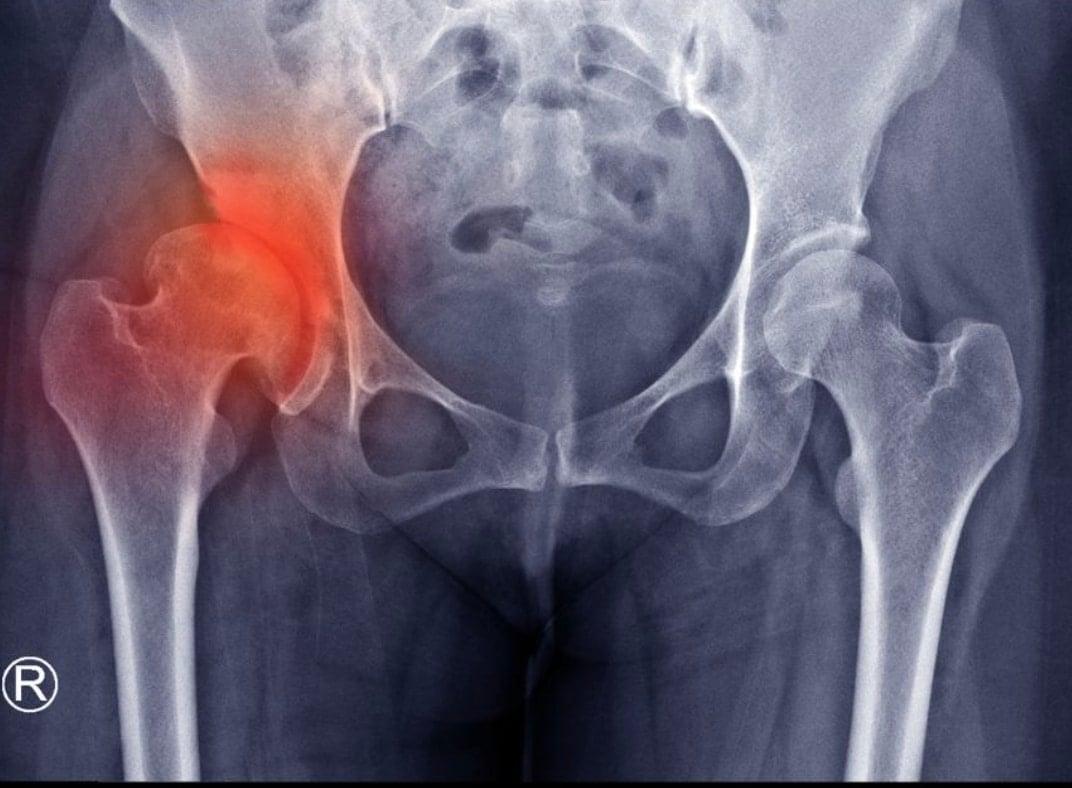

Πόνος στο ισχίο: Tι πραγματικά σημαίνει;

Ενώ η οστεοαρθρίτιδα του ισχίου συνδεόταν κυρίως με τη γήρανση, ολοένα και περισσότεροι δραστήριοι ενήλικες στα 30 και 40 τους χρόνια βιώνουν τα συμπτώματά της. Τα καλά νέα; Η έγκαιρη δράση μπορεί να κάνει τη διαφορά.

Στο κέντρο της άρθρωσης του ισχίου υπάρχει ένα στρώμα λείου χόνδρου που προστατεύει και απορροφά τους κραδασμούς καθώς τα οστά κινούνται. Όταν αυτός ο χόνδρος αρχίζει να λεπταίνει ή να φθείρεται, τα οστά τρίβονται μεταξύ τους, προκαλώντας πόνο, δυσκαμψία, φλεγμονή και τελικά μια κατάσταση γνωστή ως οστεοαρθρίτιδα του ισχίου (ή αλλιώς κοξάρθρωση).

Φωτογραφία: papoutsis-ortho.gr